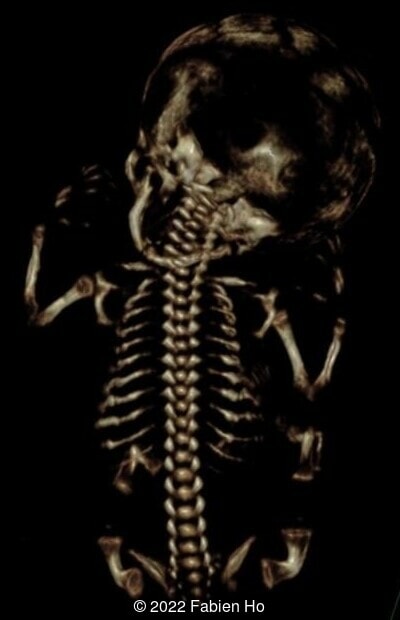

The prenatal CT scan showed:

- Low bone density of skull and lower limbs

- Moderately narrowed and bell-shaped thorax

- Numerous bone calluses of the posterior arcs of the ribs

- Normal bone density of the spine

- No platyspondyly

- Normal pelvis without iliac spine or other anomaly

- Very short long bones with curved femurs, tibias and fibulas. The curvature of the long bones reaches a 90° angle concerning for fracture. Upper limbs are moderately curved without fracture.